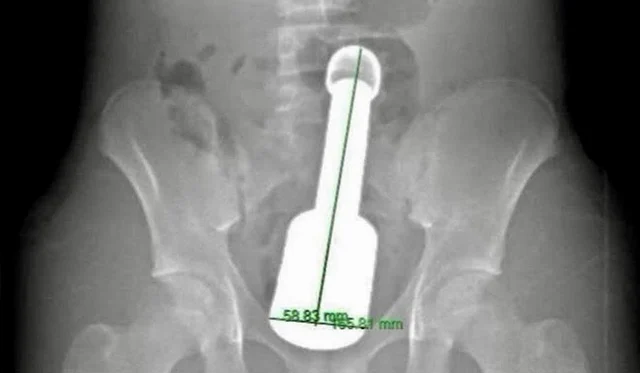

의료진은 환자의 상태를 평가하기 위해 X-ray 촬영을 진행했습니다. 촬영 결과, 직장 깊숙이 금속성 이물질이 박혀 있는 것을 발견했습니다. 이물질은 길이 약 18cm, 지름 약 6cm의 금속 절구로, 골반 장기를 압박하고 있는 상황이었습니다. 이러한 발견은 의료진에게 큰 충격이었고, 즉각적으로 다학제 협의회를 소집하기로 결정했습니다.